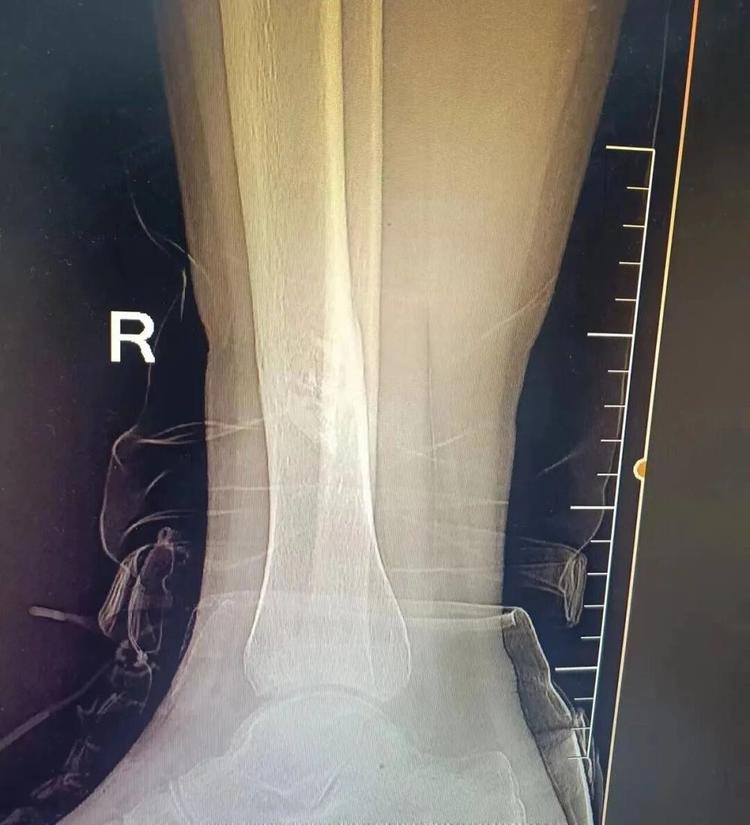

患者王某因意外导致胫骨中下段骨折,家人心急如焚地带他来到益民中西医结合诊所,经仔细检查后,运用陈氏正骨手法为其精准复位,配合特制膏药外敷。在系统调理下,小王的骨骼日渐愈合,恢复情况良好。

▲治疗前后对比